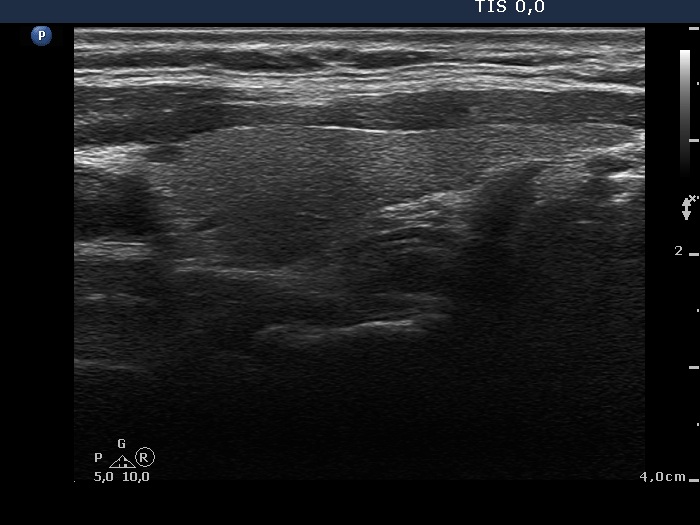

Intranodular hyperechogenic figures - case 624 (ultrasonographic picture 8)

Left lobe, longitudinal scan.